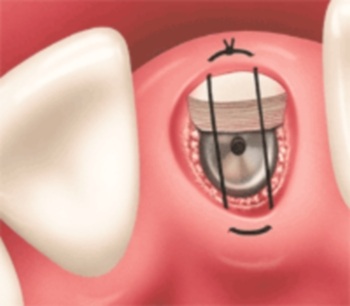

Hình 1c: Ghép Implant, nhồi thêm xương nhân tạo lên trên (nếu cần thiết), và khâu lại.